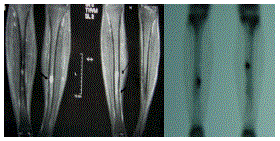

Paciente de 32 anos, do sexo masculino, praticante de natação, corrida e ciclismo, com dor em ambas as pernas há 3 semanas.

Baseado na imagem disponibilizada, qual o seu diagnóstico?